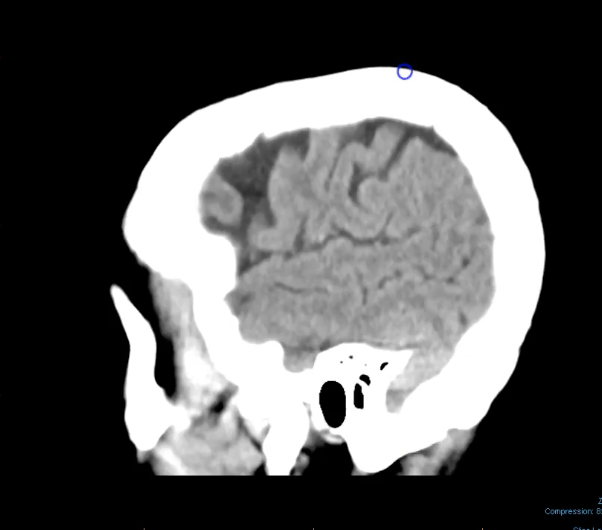

<p></p>

zygomatic arch